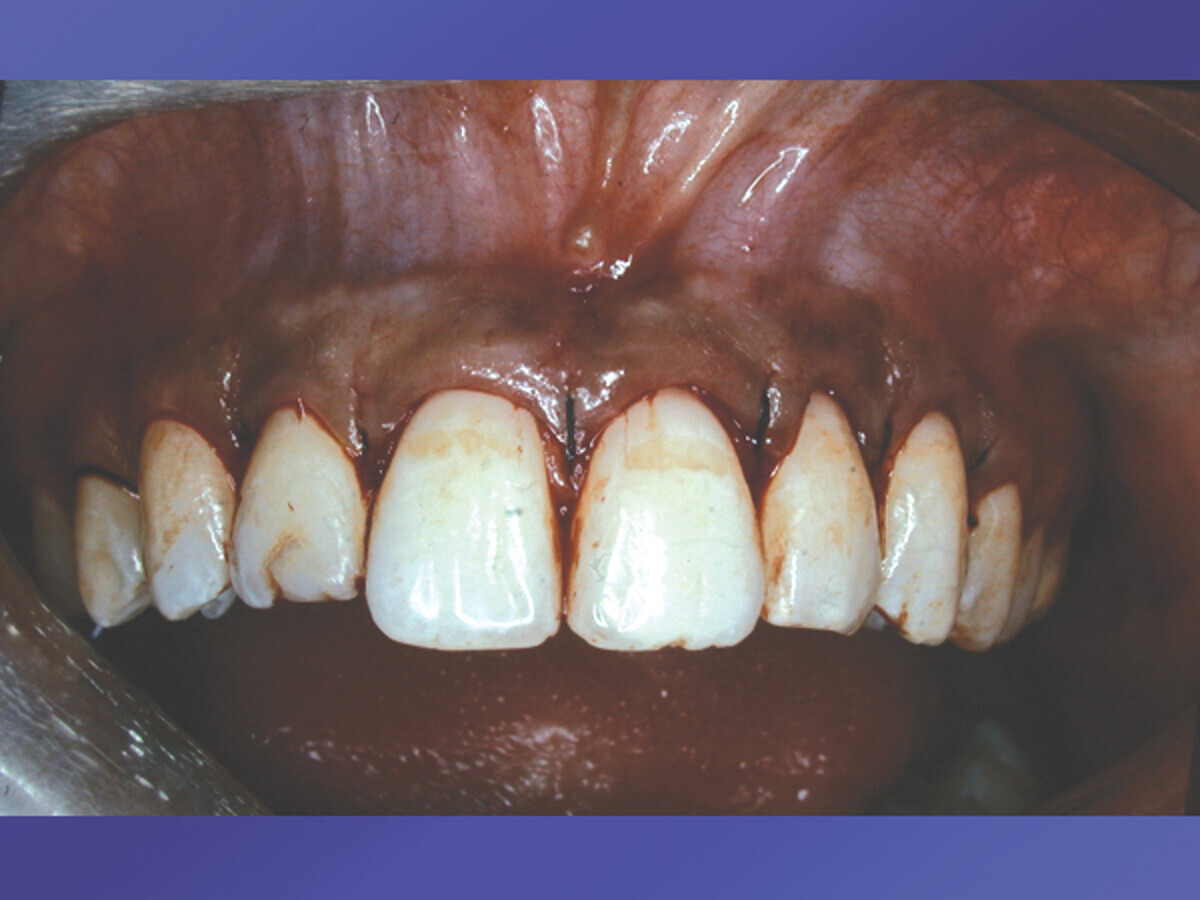

Fig. 2: Periodontal tissue repositioned sutured with sling suture technique. (Photo: Dr. David L. Hoexter)

The tissue was now placed at the desired level, usually at the symmetrical cervical height. Using the cuspid cervical height, in this case, the laterals and the centrals were positioned and sutured with a sling suture technique (Fig. 2) at the desired symmetrical level. Notice that the natural length of the incisors are exposed, but not the roots. The interproximal tissue is maintained to avoid the previously mentioned black-diamond appearing spaces that result when the interproximal tissues are removed. Notice the now exposed full enamel covering of the teeth involved, giving the length of the teeth the exposure required for the goal of “that smile” (Fig. 3). After the final stage, the young woman was ecstatic about her new bright smile. Her #7 was restored with a composite restoration. She maintains her oral health enthusiastically with oral hygiene, keeping the now healthy anterior periodontia maintained. The homogeneous color of the gingiva is symmetrical in lateral and vertical dimensions. There are no dark spaces interproximal, and the cervical symmetry of the teeth aid her ability to enjoy her glowing smile. The previously square-appearing teeth, are now restored to a natural, longer-appearing crown length, with the cervical gingiva on an even, lateral-linear appearance.

This case presentation exemplifies the “Growing Enamel” technique and its ease of use when correctly diagnosed to turn an undesirable-appearing smile into a bright, glowing and symmetrical one that the patient will love and enthusiastically maintain.